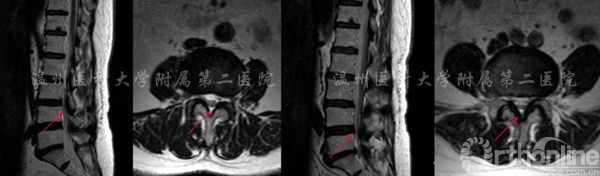

案例2

腰3/4,腰4/5椎间盘突出伴椎管狭窄,行双节段CBT螺钉固定。

左图:提示腰3/4椎管狭窄 右图:提示腰4/5椎管狭窄

术后X线显示CBT螺钉未松脱、断裂,螺钉位置良好